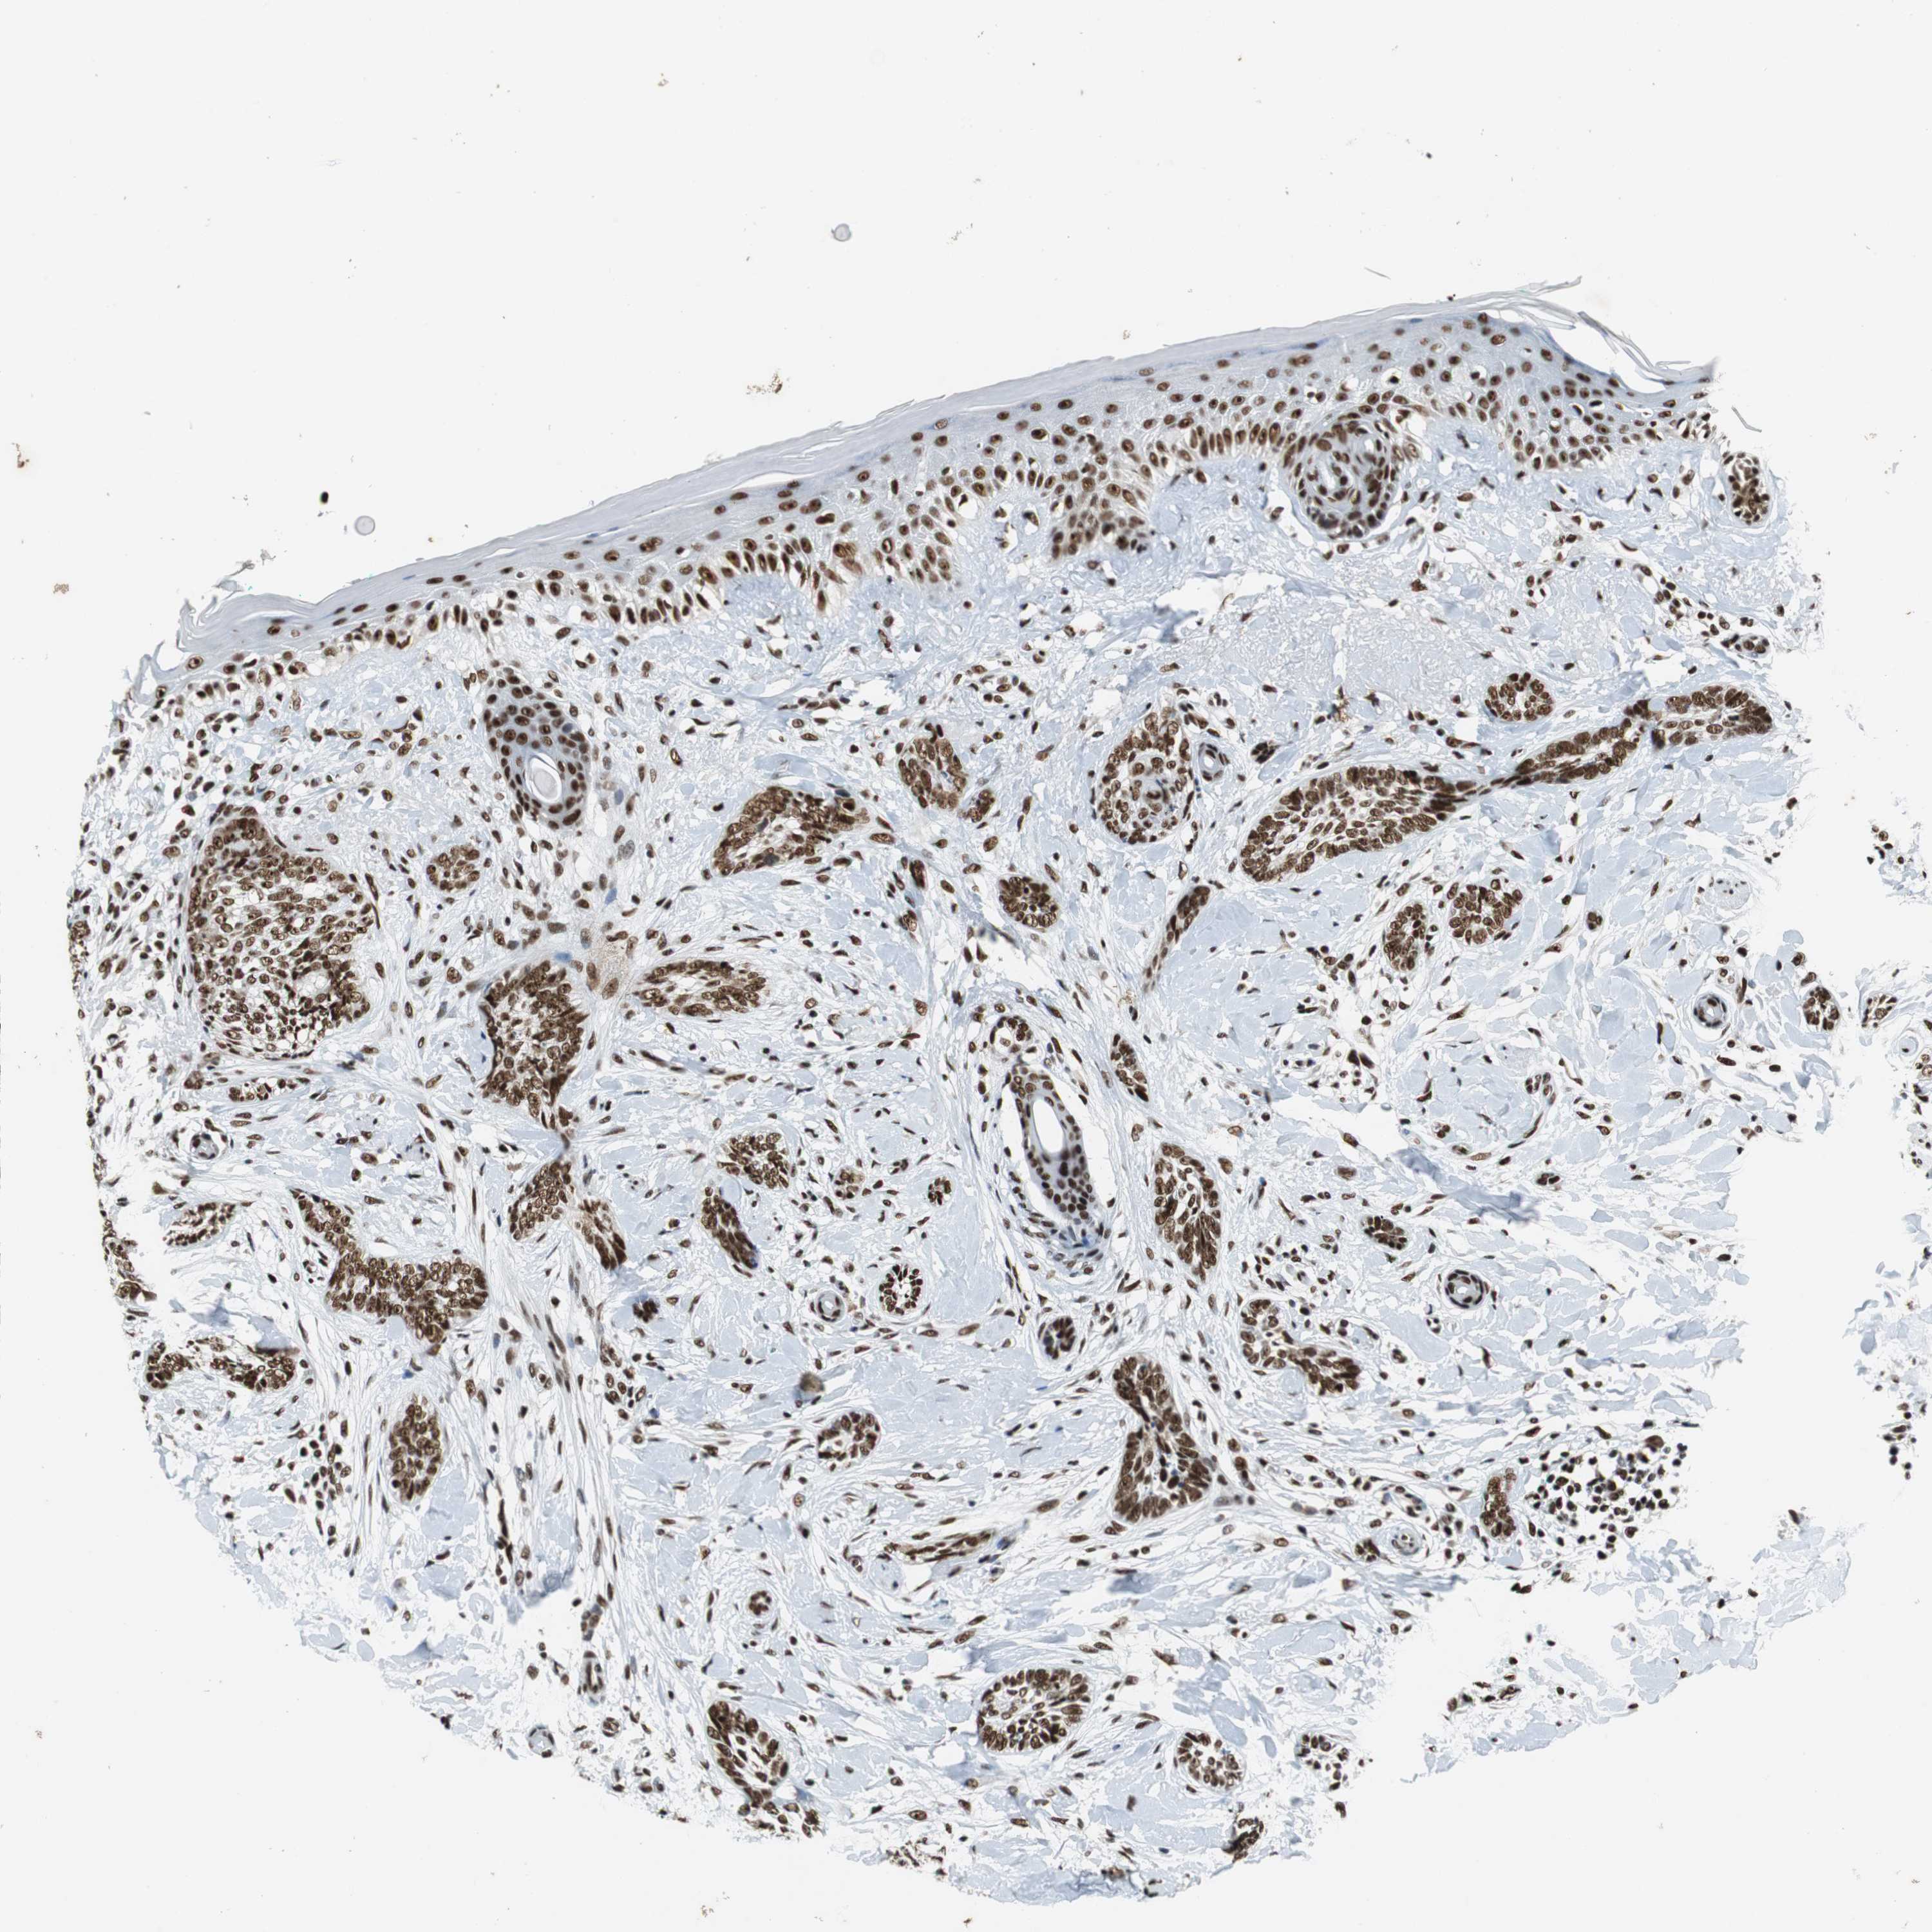

Basal cell and squamous cell cancer

SKIN CANCER - Protein expressioni

A mouse-over function shows sample information and annotation data. Click on an image to view it in a full screen mode. Samples can be filtered based on level of antibody staining by selecting one or several of the following categories: high, medium, low and not detected. The assay and annotation is described here.

Antibody stainingi

Antibody staining in the annotated cell types in the current human tissue is reported as not detected, low, medium, or high, based on conventional immunohistochemistry profiling in selected tissues. This score is based on the combination of the staining intensity and fraction of stained cells.

Each image is clickable and will lead to virtual microscopy that enables deeper exploration of all samples and also displays staining intensity scores, fraction scores and subcellular localization as well as patient and tissue information for each sample.

Antibody HPA035174

Antibody CAB005167

Staining

High

Medium

Low

Not detected

Intensity

Strong

Moderate

Weak

Negative

Quantity

>75%

75%-25%

<25%

None

Location

Nuclear

Cytoplasmic/membranous

Cytoplasmic/membranous,nuclear

Squamous cell carcinoma, NOS